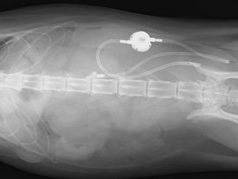

SUB(Subcutaneous Ureteral Bypass)システムとは、尿管閉塞の治療として、尿管とは別に腎臓―膀胱バイパスを設置するシステムです。

尿管ステントより径の太い2本のカテーテル(ロッキングループ腎瘻カテーテル、膀胱瘻カテーテル)のうち、ループカテーテルの先を腎盂に、

ストレートカテーテルの先を膀胱に設置し、尿管を通さずに2本のカテーテルを一旦皮下に出して、皮下に設置したポートでつなぎます。

腎臓から出た尿はポートを通り、尿管を迂回して膀胱に流れ込みます。

人工尿管(SUBシステム2.0)を設置

尿管結石を取り除き人工尿管(SUBシステム2.0)を設置しました。

SUBシステムを設置しました。